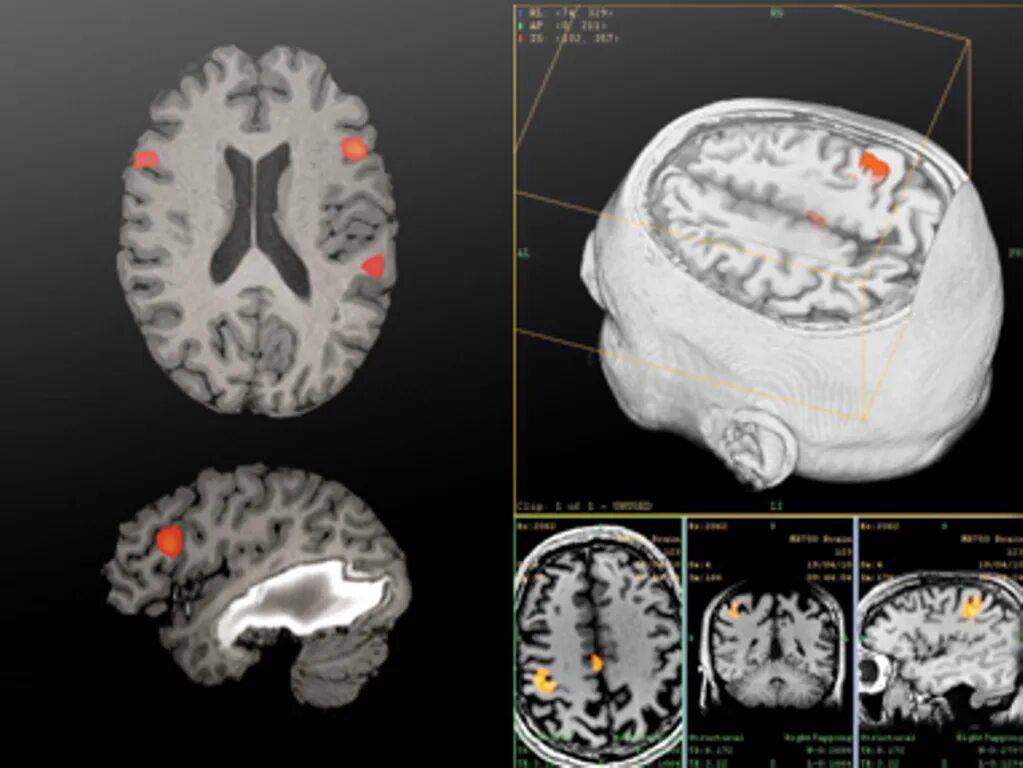

Чем отличается кт от мрт головного